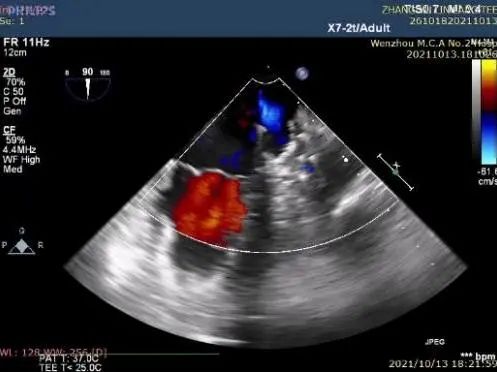

②左心耳封堵

行左心耳头位和足位造影,造影显示左心耳为菜花型。锚定区约为20mm,开口区约为24mm,依据选型原则,拟选LAmbre™2228封堵器或2430封堵器。

图1:RAO30° CRA20° 头位造影

图2:RAO30° CAU20° 足位造影

完全展开封堵器后评估:封堵盘此时置于嵴内,不符合预期。李教授通过牵拉操作,使封堵盘成功盖在嵴外,且固定盘锚定良好,非常稳定。释放后再次评估,超声及造影证实封堵器恰能完全覆盖心耳,满足COST原则,结束手术。

图8:TEE评估图

图10:释放后TEE再次评估封堵效果